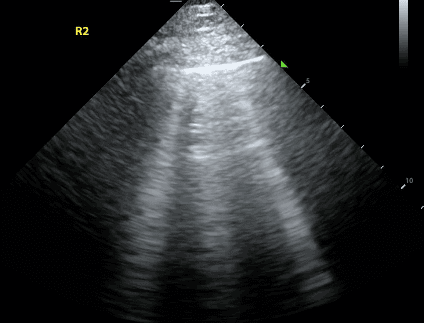

Use a high-frequency transducer, such as the linear probe. Place the probe in the anterior chest at the midclavicular line, right below the clavicle with the probe marker pointing toward the patient’s head.

Lung sliding refers to the movement of the visceral pleura when it is directly adjacent to the parietal pleura. On lung ultrasound, it has been described as the appearance of “ants moving on a log” or “shimmering” of the pleural line.

In a pneumothorax, air separates the parietal and visceral pleura. Thus, you will not be able to see movement of the visceral pleura against the parietal pleura. The absence of lung sliding is very sensitive for the diagnosis of a pneumothorax. However, it is not specific as other pathologies such as pneumonia, ARDS, and bullae can all cause absent lung sliding.